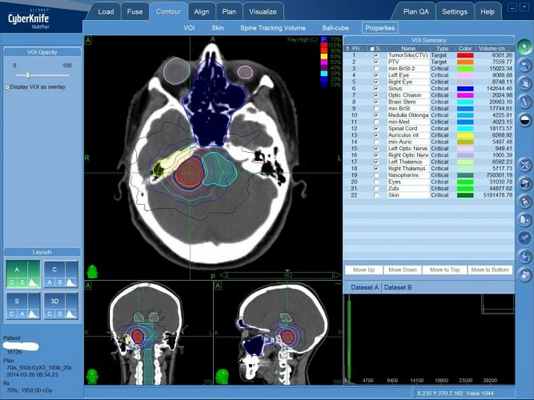

В процессе подготовки лечения на КиберНоже с помощью средств инструментальной диагностики формируется пространственная модель взаимного расположения опухоли и здоровых тканей, которая и будет являться тем объемом, в котором с помощью многочисленных отдельных тонких лучей ионизирующего излучения будет сформирована разрушающая акустическую невриному доза излучения. За доставку дозы отвечает высокоточный программно-аппаратный комплекс, который действует строго по заданному плану лечения, что позволяет максимально защитить здоровые ткани от облучения и равномерно подать значительную дозу в объем акустической невриномы.

Акустическая неврома (невринома слухового нерва): план радиохирургического лечения на КиберНоже. Красным цветом выделен объем опухоли — сюда будет подана максимальная доза ионизирующего излучения